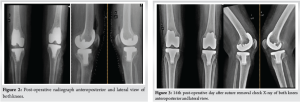

We commenced robotic-assisted TKA at our institution utilizing the Curexo-Meril Cuvis system, a fully automated robotic platform from Korea, in September 2023. This image-based ,implant specific system utilizes computed tomography scans and mill technology, featuring a pre-cut gap check that assists in addressing gaps and achieving soft tissue balance. It allows for the adjustment of implant positioning without the need for soft tissue release or excision of osteophytes. This marks our 25th case, highlighting our initial experience amid a significant learning curve. After obtaining physical fitness, the patient undergone surgery on December 08, 2023. The procedure adhered to standard robotic-assisted surgical protocols, employing kinematic alignment alongside pre- and post-cut gap assessments. Optimal balance was maintained throughout the range of motion, resulting in satisfactory patellar tracking. We utilized the Destinee Maxx-Meril cobalt-chromium-based multiradii curve femoral implant (size D), along with a titanium tibial tray (size 3) featuring an 11 mm high-flexion design polyethylene insert on both sides (Fig. 2). Intraoperative navigation confirmed satisfactory alignment, and post-operative radiographs corroborated this. The post-operative period proceeded without complications. The patient was assisted in walking with a walker 8 h after surgery. Standard post-operative protocols for antibiotic administration and deep vein thrombosis prevention were implemented. On the 5th day following surgery, the patient was discharged with detailed instructions for rehabilitation. The patient returned on the 14th post-operative day for suture removal, showing proper wound healing and no signs of infection. A check x-ray revealed satisfactory implant alignment (Fig. 3). The patient was then referred to the physiotherapy department to begin stage 2 and 3 of the rehabilitation program. There is limitation for collection of quantitative data.